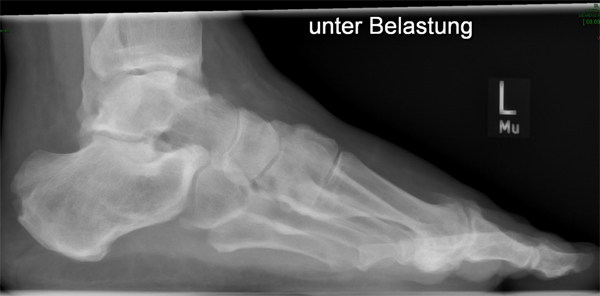

• Belastete Röntgenaufnahmen in 3 Ebenen.

Beim Hallux rigidus Stadium II beobachtet man die Ausbildung von Osteophyten dorsal, medial und lateral sowohl metatarsal als auch an der Basis des Grundphalanx bei noch ausreichender Knorpelbedeckung der plantaren Gelenkabschnitte 12. Diese führen zum Impingement, zur Einschränkung der Extension im Großzehengrundgelenk und konsekutiver Störung des Abrollverhaltens des Fußes.